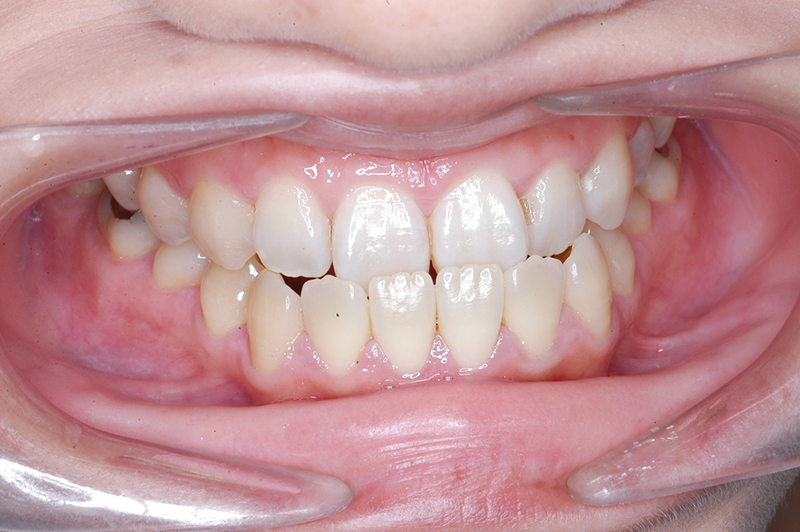

動的治療終了時

FP・IOP

批評・予后 ロウアングルのSkeletal Ⅲ級であり、下顎臼歯は近心傾斜しつつ7遠心部にはアップライトができるスペースがあると判断して、MEAWによる咬合平面の平坦化および可及的な下顎のカウンタークロックワイズローテーションによって改善を行うこととした。治療後には歯列の整直とⅠ級の咬合が得られた。(H30年9月現在で)保定開始4年経過しているが現在も咬合は安定している。